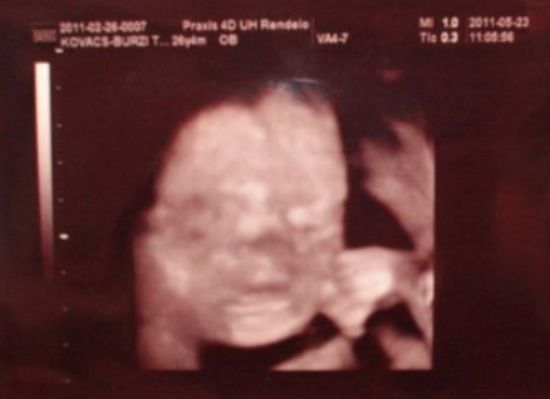

Amúgy megvizsgált teljesen rendbe talált mindent totál zárt vagyok a vérnyomás is nagyon jó és a szívhang is. Vércukor terhelés után 5,7.

Vasat írt fel mert kezdek szerinte vérszegény lenni.